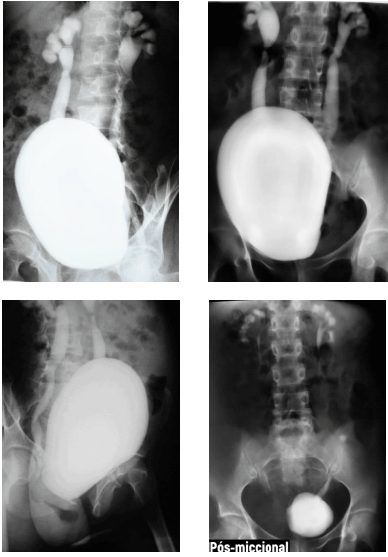

Criança de cinco anos de idade realizou exame contrastado de uretrocistografia miccional, que evidenciou os achados demonstrados nas imagens precedentes.

Acerca dos exames contrastados e das alterações do trato urinário na infância, julgue o próximo item.

O refluxo vesicoureteral grau II alcança todo o sistema coletor.

Há sinais de estenose das junções ureteropélvicas bilateralmente.

A uretrocistografia miccional, além de identificar a presença de refluxo vesicoureteral, tem a capacidade de avaliar o grau do refluxo, que, no paciente em questão, é classificado como grau II.

Algumas das indicações para a realização de uretrocistografia miccional incluem infecções do trato urinário superior de repetição, pesquisa de alterações sequelares de sondagens vesicais de demora e pesquisa de sequelas de doenças sexualmente transmissíveis em adultos.

A técnica desse exame inclui a administração venosa do meio de contraste e a realização de radiografias seriadas para avaliação da concentração e excreção do contraste pelos rins, o que permite a avaliação também das vias urinárias e da bexiga, sendo posteriormente avaliada a uretra durante a micção.